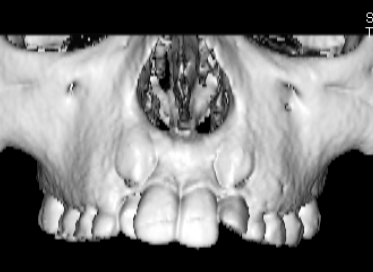

治療法:上顎急速拡大装置+クリアスナップ+フェイスマスク+上顎3番は開窓牽引CT写真にて位置確認

FX(フェイシャルアキシス)は85度なので東洋人の平均値に近く、下顎が前方に過剰成長するリスクは強くはありません。

しかしやはり上顎は劣成長で、下顎が優位な状態ではあります。

上下顎のギャップはありますが、顔面自体の幅径は良好な値を示していますので、スペース不足は拡大することによって解決できポテンシャルはあると考えられます。

左右の非対称もさほど強くありません。

検査時のレントゲン分析では、上下顎の関係は、上顎の劣成長があり下顎前突傾向という値がでておりましたが、前歯ジャンプ後はフェイスマスクの効果もあり、上下顎の関係は正常化しています。

上顎が若干優位になっていますので、今後の下顎の成長のための貯金になっているくらいです。